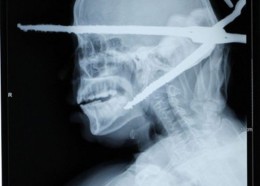

Чудни ренгенски снимки